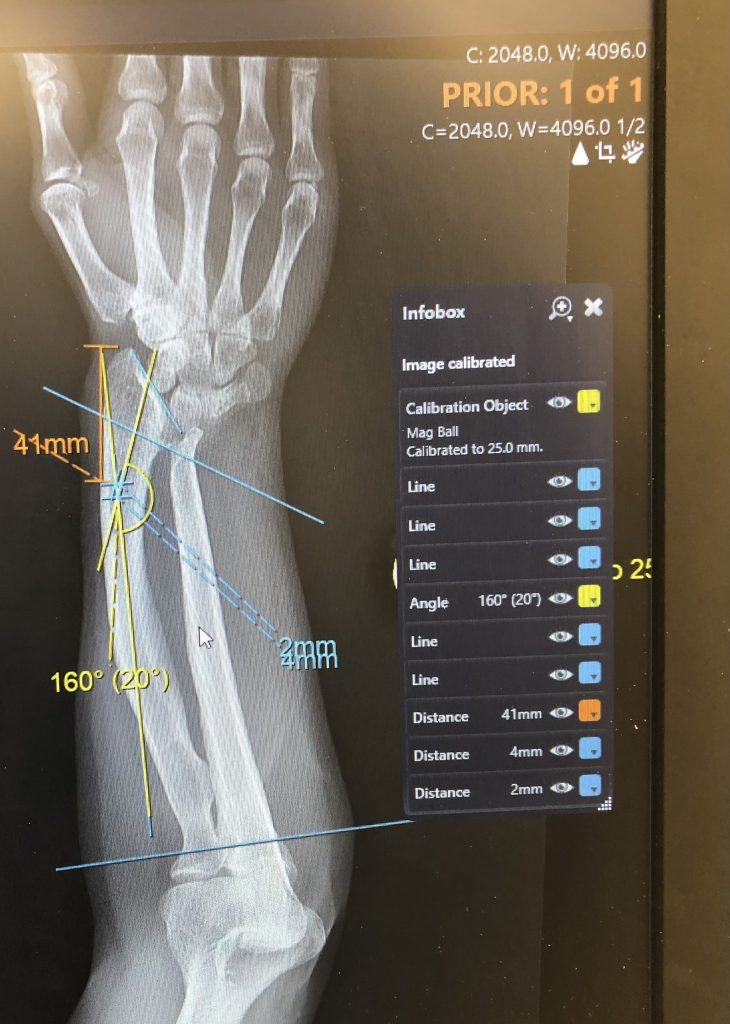

Dr. Rozbruch and his team made a dream come true. I was born with a deformity of both my wrists and forearms. They were bowed and abnormally short. The deformities plagued me every day. I am 57. In August 2022, I had my first consultation with Dr. Rozbruch. He told me he could help me!

It was a long road, 6 surgeries, and a combined 352 days in an external fixator (TSF). First the left arm and then the right. Dr. Rozbruch and his incredible team were there every step of the way. They answered every question and email. They are so talented and so kind.

Dr. Rozbruch makes it seem so effortless, but I know how special his skills are. I am forever grateful. He straightened and lengthened both of my forearms. A true miracle!